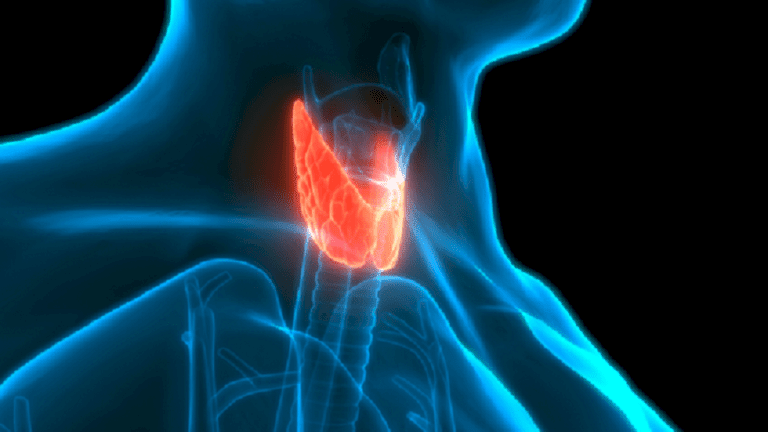

مواد سامة للغدة الدرقية

وتشير الخبيرة في مقابلة مع موقع doctorpiter.ru، إلى أن الغدة الدرقية مسؤولة عن إنتاج الهرمونات وتتحكم في عملية التمثيل الغذائي . وأي خلل في عملها يؤدي إلى زيادة أو انخفاض في الوزن، وكذلك فقدان الاحساس بالحر واضطراب النبض. وهناك مواد غذائية تعتبر سامة للغدة الدرقية.